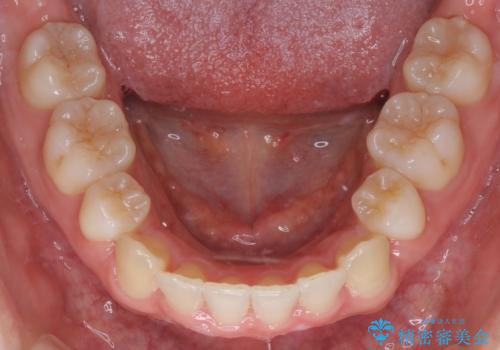

- 口元をさげたいという主訴で来院されました。4番の歯を4本抜歯し、審美装置にて治療をしました。

抜歯をしたことで口元の突出感が改善しました。約2年を予定していた矯正ですが、約1年という短い期間で終了できました。